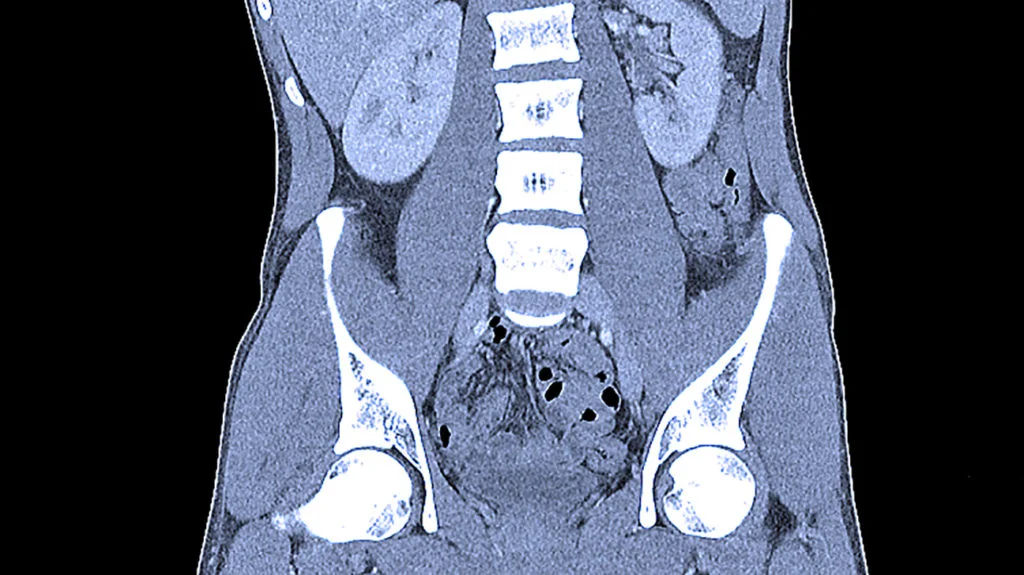

КТ черевної порожнини – діагностичний метод, який візуалізує стан органів черевної порожнини та заочеревинного простору разом із судинами та лімфатичними вузлами «пошарово», з мінімальним кроком від 0,5 мм. Комп'ютерна томографія дає високоточне тривимірне зображення й виявляє початкові невеликі патологічні зміни в органах, які неможливо виявити за допомогою інших досліджень.

Комп'ютерна томографія (КТ) черевної порожнини – це метод діагностики, що дозволяє отримати детальні тривимірні зображення органів черевної порожнини та заочеревинного простору. КТ використовує рентгенівські промені для створення пошарових зображень з мінімальним кроком, що забезпечує високу точність виявлення навіть невеликих патологічних змін. Завдяки цьому методу лікарі можуть оцінити структуру органів, їх функціонування та наявність захворювань або патологічних процесів.

Цей метод дозволяє оцінити структуру та стан внутрішніх органів, а також виявити зміни, які можуть бути недоступними для інших методів діагностики. КТ черевної порожнини використовується для виявлення патологій у різних органах та тканинах черевної порожнини, включаючи:

- органи шлунково-кишкового тракту (печінка, підшлункова залоза, шлунок, товстий і тонкий кишечник, жовчний міхур, селезінка);

- органи заочеревинного простору (наднирники, нирки, судини, сечовидільна система, лімфатичні вузли).